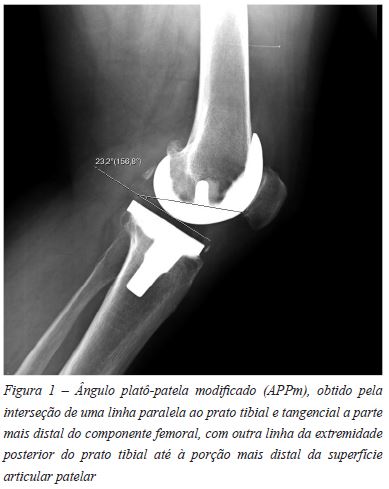

Para a avaliação radiográfica da altura patelar existem diversos métodos descritos na literatura: Insall-Salvati, Blackburne-Peel, Caton-Deschamps e Blumensaat são os mais conhecidos10. O ângulo platô-patela é uma alternativa válida para a avaliação da altura patelar, apresenta correlação com os métodos tradicionais11 e foi adaptado e validado para a avaliação da altura patelar após a artroplastia total do joelho12. O ângulo platô-patela modificado (APPm) (Figura 1) é obtido pela interseção de uma linha paralela ao prato tibial e tangencial a parte mais distal do componente femoral, com outra linha da extremidade posterior do prato tibial até à porção mais distal da superfície articular patelar. São considerados valores normais os compreendidos entre 21 e 29 graus.

As medições foram realizadas pelo mesmo autor em incidências de perfil, com o joelho em >30° de flexão, utilizando o APPm.